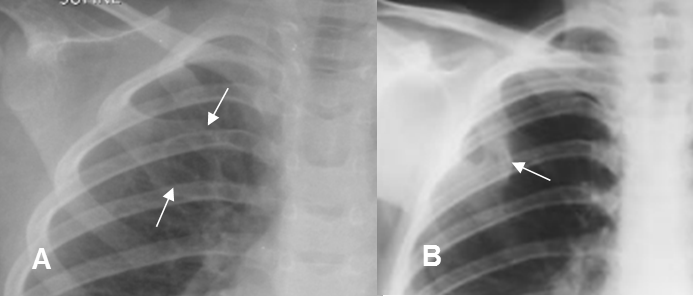

La tomografía axial computarizada (TAC) es útil para identificar lesiones ocultas, por la superposición de estructuras. Las reconstrucciones son de mucha utilidad, ya que permiten la valoración tridimensional. (Fig 13).

Fig 13. Fractura oculta.

A: Rx PA. Interposición de la silueta cardiaca y aorta descendente, que impide la valoración de la columna dorsal inferior.

B: TAC axial. Fractura no sospechada en la Rx, de la unión costovertebral izquierda.